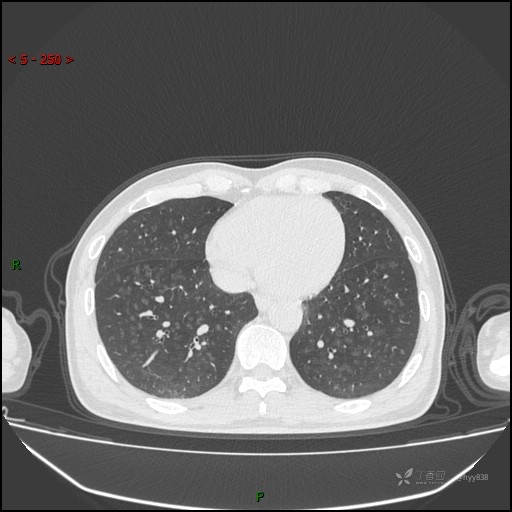

呼吸科电话会诊病例:过敏性肺炎 VS 吸烟相关间质性肺炎 VS 尘肺……结果公布~

性别:男

年龄:55岁

简要病史:渐进性呼吸困难。

胸部CT平扫

电焊工尘肺 (2)